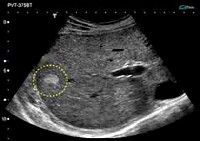

Основную роль в диагностике играют инструментальные методы исследования. УЗИ органов брюшной полости позволяет визуализировать образование, определить его размеры, границы, оценить состояние соседних органов. Выявляются единичные или множественные четко ограниченные гиперэхогенные очаги. Под ультразвуковым контролем проводится пункционная биопсия печени с последующим морфологическим исследованием биоптатов. Данный метод позволяет определить тип опухолевых клеток, степень их дифференцировки и отличить от злокачественной патологии.

При подозрении на гемангиому печени проводится ангиография (оцениваются особенности кровотока в образовании, устанавливается связь опухоли с сосудами печени), а также допплерография фокального образования.